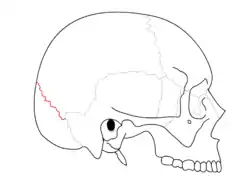

Coronal suture. It separates the parietal bones and the frontal bone. Squamosal suture. It separates the parietal bones and the temporal bone.

Squamosal suture. It separates the parietal bones and the temporal bone. Lambdoid suture. It separates the parietal bones and the occipital bone.

Parietal bone Trajectory of the missile through President Kennedy's skull. The bullet struck posterior part of his right parietal bone from behind.

Trajectory of the missile through President Kennedy's skull. The bullet struck posterior part of his right parietal bone from behind.